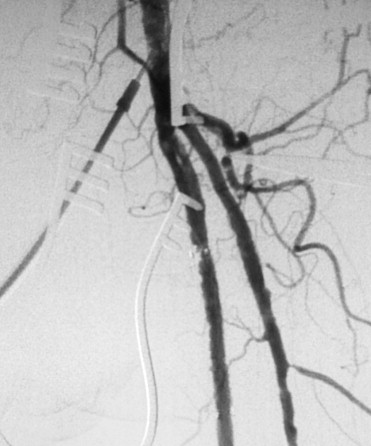

Recanalization by endarterectomy of the superficial femoral artery ostium is ...

Figure 3.

Recanalization by endarterectomy of the superficial femoral artery ostium is followed by distal endovascular therapy.

All procedures were performed under local anesthesia. One patient with dementia (Case 6) was administered oral sedative drugs. The most proximal ostial portion of the SFA was managed by an open direct endarterectomy, which involved making a 4–6-cm recanalization with an approximately 7-cm skin incision. If needed, the common femoral and proximal deep femoral arteries were also treated by endarterectomy. The materials removed from the SFA ostium varied from a soft old thrombus (Fig. 2A) to hard calcified intima-media (Fig. 2B). After almost all of the arteriotomy was closed with or without a vein patch, the clamper that had intercepted the common femoral and deep femoral arteries was moved to the SFA orifice. After circulation through the deep femoral artery was restored, the remnant of the arteriotomy was used as an entrance for EVT for the remaining occluded distal part. A guidewire, followed by an angioplasty balloon catheter, was directly introduced. When the guidewire did not easily pass the hard lesions, the balloon catheter was advanced just proximal to the lesion. Using this approach, the resistance was directly sensed, and an adequate pushing power was used to cross the hard lesions. After identifying the distal boundary of the occlusion, ballooning was performed at the most distal site first. Ballooning was performed step by step toward a proximal direction. After ballooning of the full length of the occluded artery, the catheter was pulled out from the artery, and then debris was flushed out by the backflow. Before the total closure of the arteriotomy, an introducer was placed and fixed by a snaring suture for angiography. After the clamper at the SFA orifice was removed, angiography was performed. If needed, additional EVT of the ilio–femoro–poplito–tibial area was performed. A nitinol stent was placed at the residual stenosis of SFA and/or the iliac portion (Fig. 3). In SFAs, in particular, stents were implanted in an area of residual stenosis >30% and pressure gradient >10 mmHg, with or without dissection. The stents placed in the SFAs avoided distal nonstenting zones in all cases.